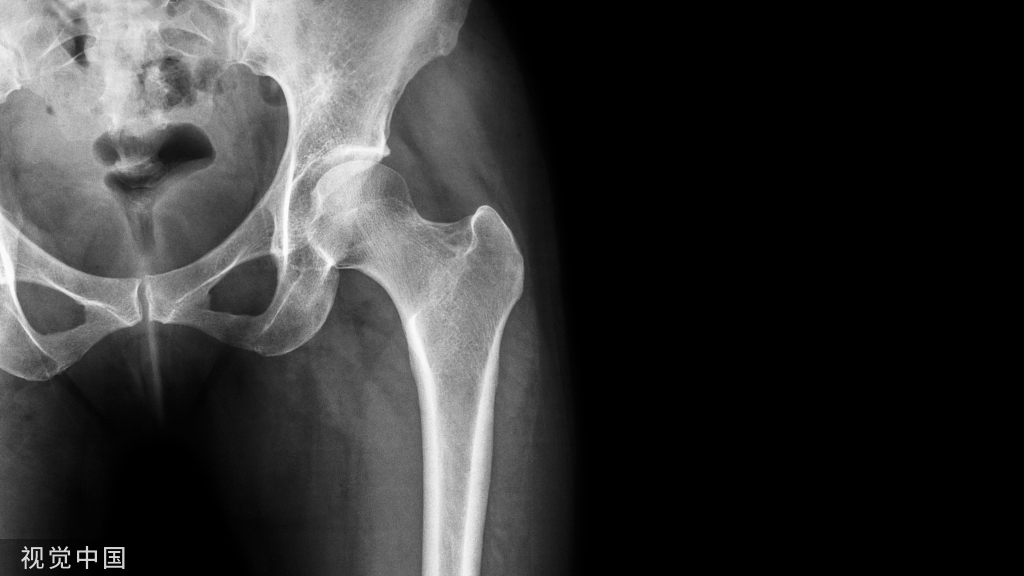

根据数据显示,每年全国近100万例患者需行人工关节置换手术换上人工关节,由它替代人体受损的膝关节、髋关节,来帮助人们正常走路、运动。而近几年,中国的人工关节置换手术量已经超过每年60万台,并且正在以平均每年超过15%-20%的速度递增。这说明了人工关节置换手术在中国的普及程度越来越高,也反映了人们对健康的重视程度不断提高。

为了进一步推动关节外科标准化技术的发展,避免临床上并发症,由德医主办的【人工关节置换规范化手术操作精讲班】于2023年12月23-24日在郑州市召开。